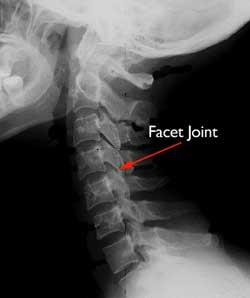

As the facet joints experience increased pressure, they also begin to degenerate and develop arthritis, similar to what may occur in a hip or knee joint. The smooth, slippery articular cartilage that covers and protects the joints wears away.

If the cartilage wears away completely, it can result in bone rubbing on bone. To make up for the lost cartilage, your body may respond by growing new bone in your facet joints to help support the vertebrae.

Over time, these bone overgrowths — called bone spurs — may narrow the space for the nerves and spinal cord to pass through (stenosis). Bone spurs may also lead to decreased range of motion in the spine.

X-rays. X-rays provide images of dense structures, such as bone. An X-ray will show the alignment of the bones along your neck. It can also reveal degenerative changes in your cervical spine — such as the loss of disk height or the presence of bone spurs.

- Cervical facet joint block. In this procedure, a combination of steroid and anesthetic medicine is injected into the capsule of the facet joint. The facet joints are located in the back of the neck and provide stability and movement. These joints can develop arthritic changes that may contribute to neck pain.